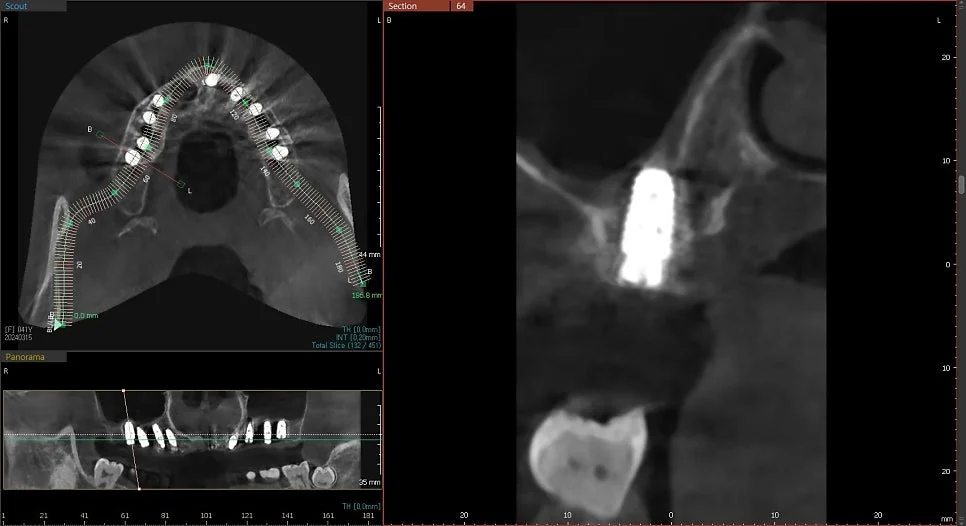

CBCT 단면 – 각 임플란트 개별 검증

CT 상에서 하얀색인 임플란트가 1. 온전히 뼈 안에 잠기게(1~2mm 깊게) 그리고 2. 가급적이면 입천장 쪽으로 식립되었다면 잘 심긴 임플란트입니다. (입술 쪽 뼈는 쉽게 흡수됩니다ㅜ)